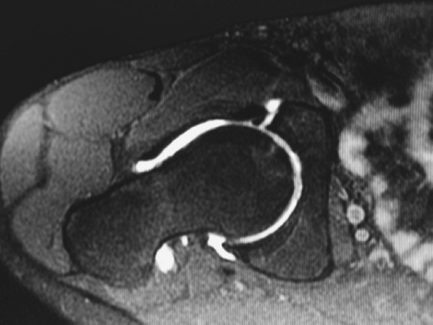

inflammatory tissue. MRI arthrography, consisting of the direct

the diagnosis of labral and chondral pathology of the hip (Fig. 2-20).

Figure 2-20 MRI arthrography of the hip demonstrating anterior labral tear.